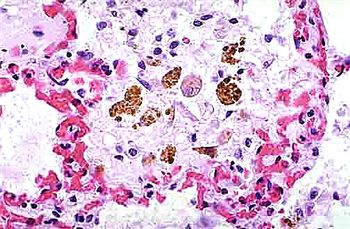

小鼠肺泡巨噬細(xì)胞的應(yīng)用

巨噬細(xì)胞,作為免疫系統(tǒng)中的重要成員,以其獨特的吞噬能力和廣泛的生物學(xué)功能,在機(jī)體的免疫防御、組織修復(fù)、炎癥反應(yīng)調(diào)控等方面發(fā)揮著至關(guān)重要的作用。

吞噬作用 巨噬細(xì)胞最顯著的功能是其強(qiáng)大的吞噬能力。它們能夠伸出偽足包圍并吞噬細(xì)菌、衰老細(xì)胞、凋亡細(xì)胞、細(xì)胞碎片及病原體等,形成噬體或吞噬小泡,隨后將其消化分解。這一過程不僅有助于清除體內(nèi)的有害物質(zhì),還能激活其他免疫細(xì)胞對病原體作出反應(yīng)。